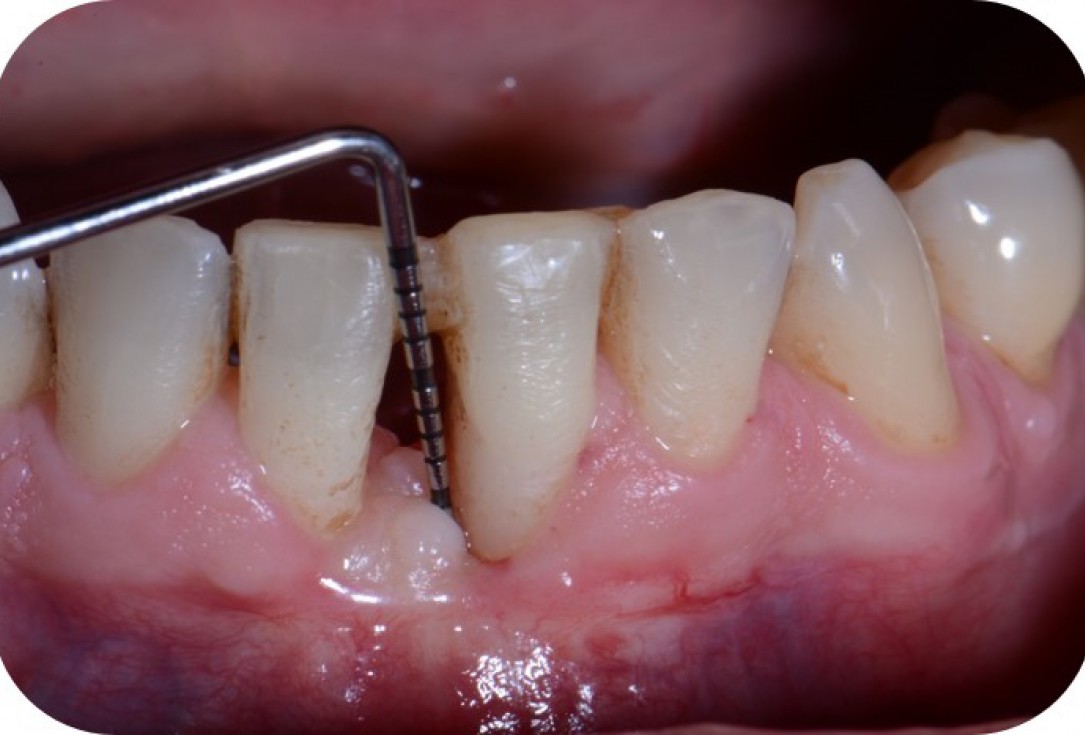

10/12 - Clinical situation 3 months post-operative with 5 mm probing pocket depth.Two-wall intrabony defect treated using cerabone® and Straumann® Emdogain® - Dr. D. Rakasevic & Prof. Dr. S. Jankovic